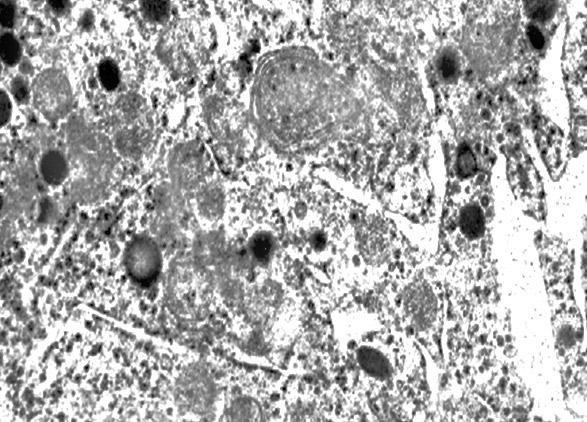

MICROAUTOFAGIA

I focolai di microautofagia si ritrovano frequentemente commisti a mitocondri disfunzionali e a reticolo- endoplasmatico in stato di stress.

Essi sono di piccole dimensioni, appaiono come vescicole, delimitate da una membrana a doppio strato, immerse nel citosol e

ricolme di materiale amorfo oppure di materiale amorfo commisto a frammenti filamentosi.